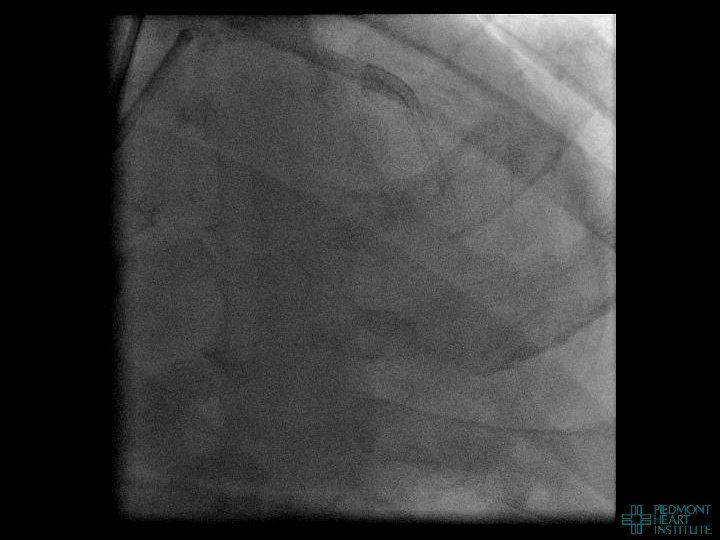

Coronary Perforation Methods of Patient Management • Dual Catheter (‘Ping Pong’) Technique • Prolonged

Coronary Perforation Methods of Patient Management • Dual Catheter (‘Ping Pong’) Technique • Prolonged balloon inflation and covered stents • Reversal of anticoagulation — Know contradictions to protamine sulfate for UFH; Avoid bivalirudin, LMWH — Reserve GP 2 b 3 a inhibition until successful crossing and wire change-out Embolization • — Coil, gelfoam, methacrylate, autologous blood/fat • Microcatheter Occlusion • Confirmation of successful management — Contralateral injection — Right heart catheterization — Echocardiogram — Contrast echocardiography